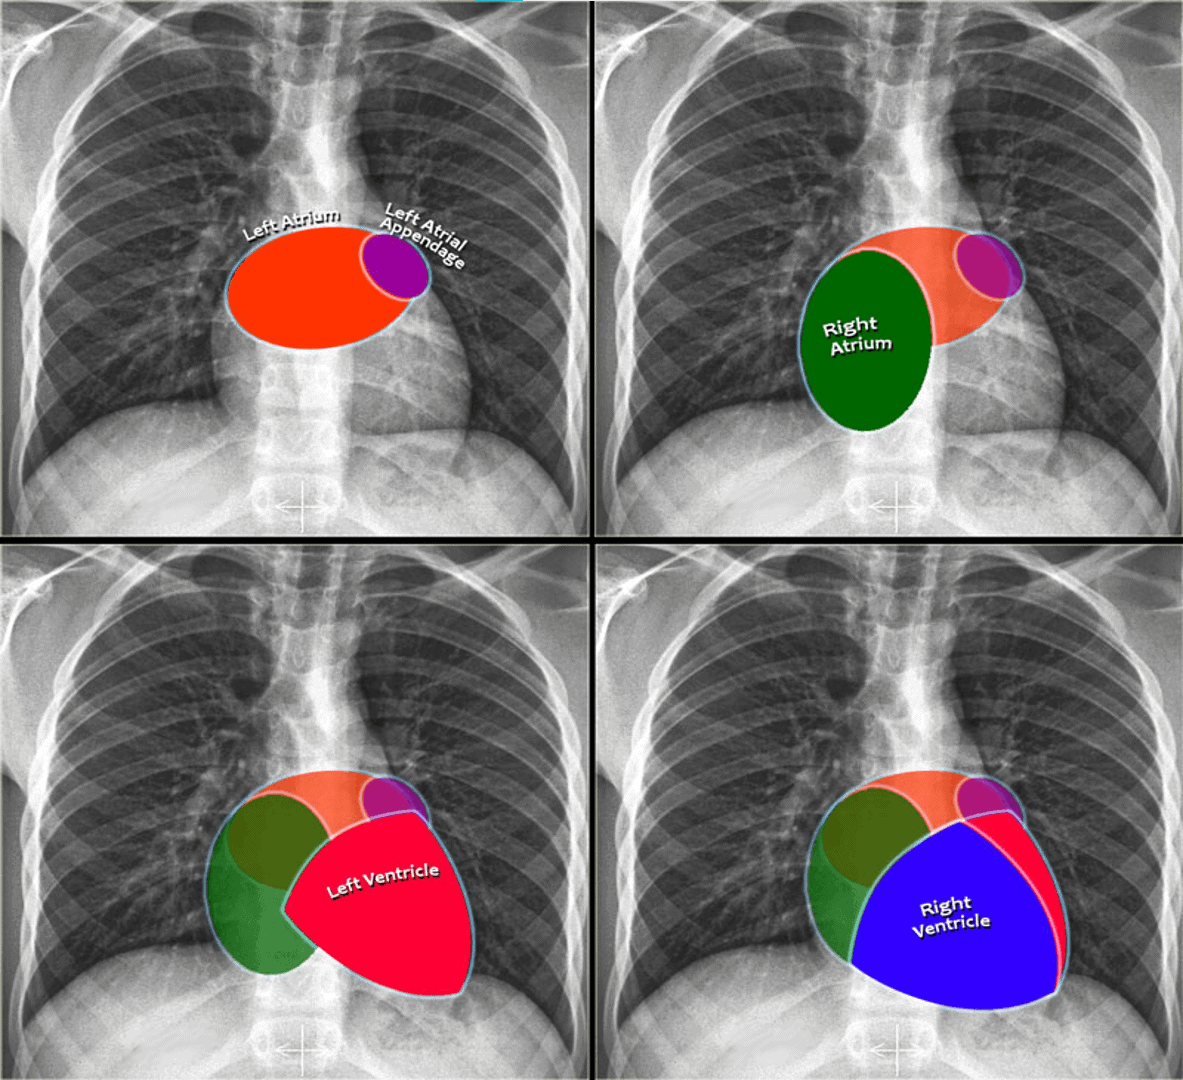

1. Giải phẫu x-quang

+ Tâm nhĩ trái (Left atrium): cấu trúc nằm sau nhất, nhận máu từ các tĩnh mạch phổi (chạy gần như theo phương ngang, hướng về tâm nhĩ trái). Tiểu nhĩ trái (hình máu tím) đôi khi có thể biểu hiện là 1 phần nhỏ lồi ra, ngay dưới thân động mạch phổi trái. Giãn nhĩ trái trên phim chụp thẳng biểu hiện lồi bờ tim trên – phải và góc tạo bởi phế quản gốc 2 bên (góc carina) là góc tù / Trên phim nghiêng thấy lồi ra của bờ tim sau trên.

+ Tâm nhĩ phải (Right atrium): nhận máu từ tĩnh mạch chủ trên và tĩnh mạch chủ dưới. Giãn nhĩ phải sẽ gây lồi bờ tim phải.

+ Tâm thất trái (Left ventricle): nằm ở bên trái và ở phía sau so với tâm thất phải. Giãn thất trái sẽ biểu hiện lồi bờ tim trái / Trên phim nghiêng thấy lồi bờ tim sau dưới.

+ Tâm thất phải (Right ventricle): nằm ở trước nhất và nằm sau xương ức. Giãn thất phải sẽ biểu hiện lồi bờ tim trái.

+ Tâm nhĩ trái (Left atrium): tạo lên bờ tim sau – trên. Giãn nhĩ trái => lồi bờ tim sau – trên.

+ Tâm thất trái (Left ventricle): tạo lên bờ tim sau – dưới. Giãn nhĩ trái => dịch chuyển bờ tim về phìa sau.

+ Tâm thất phải (Right ventricle): nằm ở phía dưới khoảng sáng sau xương ức. Lớn thất phải => làm mờ khoảng sáng sau xương ức.